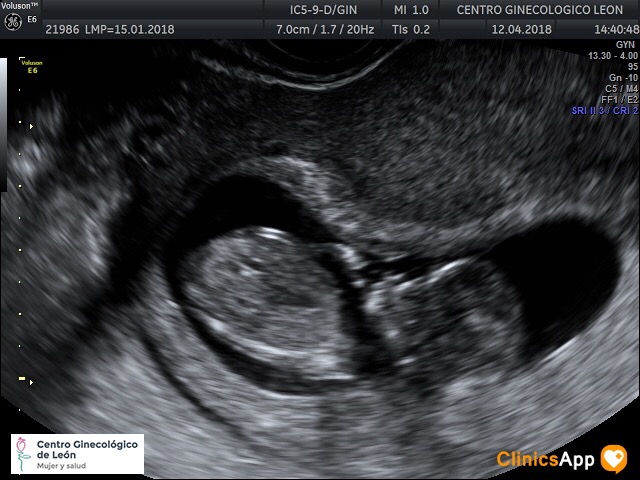

Ecografías del 12 de abril de 2018